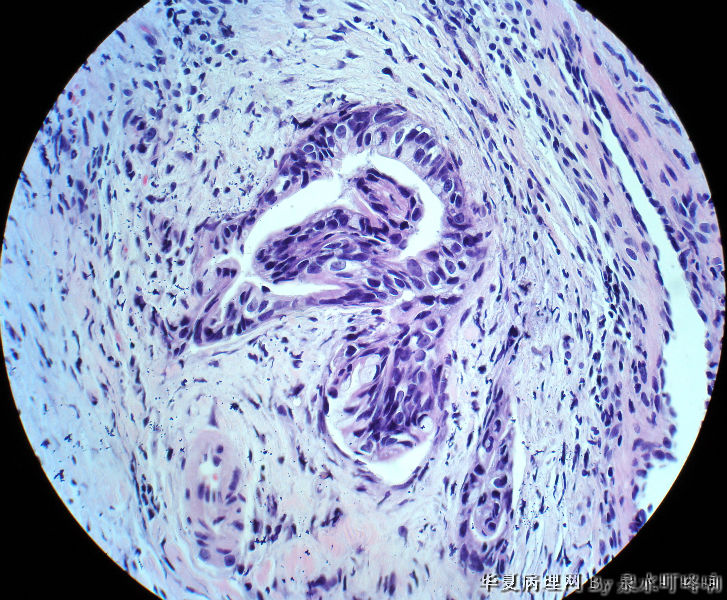

直肠活检

女,49岁,大便变细2年,结肠镜示距肛门5厘米可见溃疡形成,弥漫肠管全周。

腺癌

纤维组织中可见异型腺体浸润,诊断腺癌。

可见异型腺体,疑为直肠腺癌

理论上算腺癌了,但实际工作这么少的腺体,粘膜表面异形不明显,心里有点忐忑啊

分化较好的腺癌。